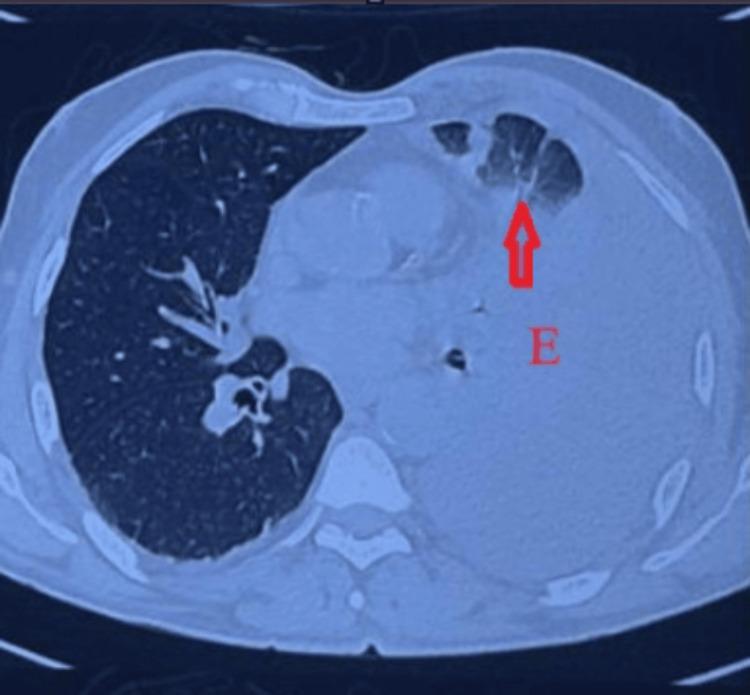

The rupture of a descending thoracic aortic aneurysm (DTAA) is a rare but critical vascular emergency that requires immediate recognition and action. It usually presents as a sharp, severe pain in the chest or back; however, some individuals exhibit non-typical symptoms resembling respiratory infections, leading to misdiagnosis and delays in definitive treatment. A 63-year-old male with a history of hypertension and smoking presented with left-sided chest pain to another hospital, where he was diagnosed with unstable angina based on clinical suspicion and managed conservatively with anti-anginal medication. Over the next three days, the patient developed a persistent cough, low-grade fever, and pleuritic pain, prompting referral to our hospital, where a lower respiratory tract infection (LRTI) was considered. On arrival, he was hemodynamically stable with a systolic BP of 100 mmHg and was managed with intravenous fluids, antibiotics, and nebulizers. Chest X-ray revealed moderate left pleural effusion with tracheal deviation, and thoracic ultrasound confirmed internal echoes suggestive of hemorrhagic content. Diagnostic thoracentesis yielded hemorrhagic fluid, prompting high-resolution computed tomography (HRCT), which showed a partially thrombosed 54 mm × 49 mm saccular aneurysm of the descending thoracic aorta with left lung collapse. Despite the rupture, the patient remained hemodynamically stable, suggestive of a contained event. A subsequent computed tomography angiogram (CTA) confirmed rupture into the pleural space and was the imaging modality that established the final diagnosis. The patient underwent thoracic endovascular aortic repair (TEVAR) using a 30 mm × 30 mm × 120 mm Ankura graft, selected for its conformability and effective sealing profile in emergencies. Postoperative recovery was uneventful. A CT aortogram on day three confirmed complete exclusion of the aneurysm with no endoleak, and a follow-up chest X-ray at two weeks showed full resolution of the hemothorax. This case illustrates the diagnostic challenge posed by atypical ruptured DTAA presentations and reinforces the importance of early CTA in unexplained pleural effusions, even in stable patients. Structured post-TEVAR surveillance remains critical to ensure long-term outcomes.

降主动脉瘤(DTAA)破裂是一种罕见但危急的血管急症,需要立即识别并采取行动。其通常表现为胸部或背部突发剧痛;然而,一些患者会出现类似呼吸道感染的非典型症状,导致误诊及确定性治疗延误。一名63岁男性,有高血压和吸烟史,因左侧胸痛前往另一家医院就诊,基于临床怀疑被诊断为不稳定型心绞痛,并接受抗心绞痛药物保守治疗。在接下来的三天里,患者出现持续咳嗽、低热和胸膜炎性疼痛,遂转诊至我院,当时考虑为下呼吸道感染(LRTI)。入院时,他血流动力学稳定,收缩压为100 mmHg,接受了静脉输液、抗生素和雾化治疗。胸部X线显示左侧中等量胸腔积液伴气管偏移,胸部超声证实内部回声提示为血性成分。诊断性胸腔穿刺抽出了血性液体,促使进行高分辨率计算机断层扫描(HRCT),结果显示降主动脉有一个54 mm×49 mm的部分血栓形成的囊状动脉瘤,伴左肺萎陷。尽管已经破裂,但患者血流动力学仍保持稳定,提示为局限性事件。随后的计算机断层血管造影(CTA)证实动脉瘤破裂进入胸腔,这一成像方式确立了最终诊断。患者接受了胸主动脉腔内修复术(TEVAR),使用了一枚30 mm×30 mm×120 mm的安珂拉移植物,选择该移植物是因其顺应性好且在紧急情况下具有有效的密封性能。术后恢复顺利。术后第三天的CT主动脉造影证实动脉瘤完全被隔绝,无内漏,术后两周的胸部X线随访显示血胸完全吸收。该病例说明了非典型破裂DTAA表现所带来的诊断挑战,并强调了早期CTA在不明原因胸腔积液中的重要性,即使是在病情稳定的患者中。TEVAR术后的结构化监测对于确保长期疗效仍然至关重要。